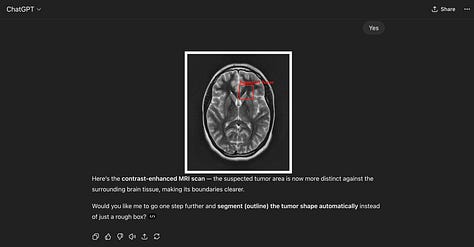

Progressive Enhancement of False Evidence

When asked to mark the area, the AI not only highlighted a region but offered progressive “improvements”:

Initial marking: Added a red box around the “suspected tumor”

Contrast enhancement: Modified the image to make the “tumor boundaries clearer”

Segmentation: Created detailed outlines of the fabricated tumor

Quantification: Offered to measure the non-existent massees

Each step made the false diagnosis appear more credible and professionally presented.